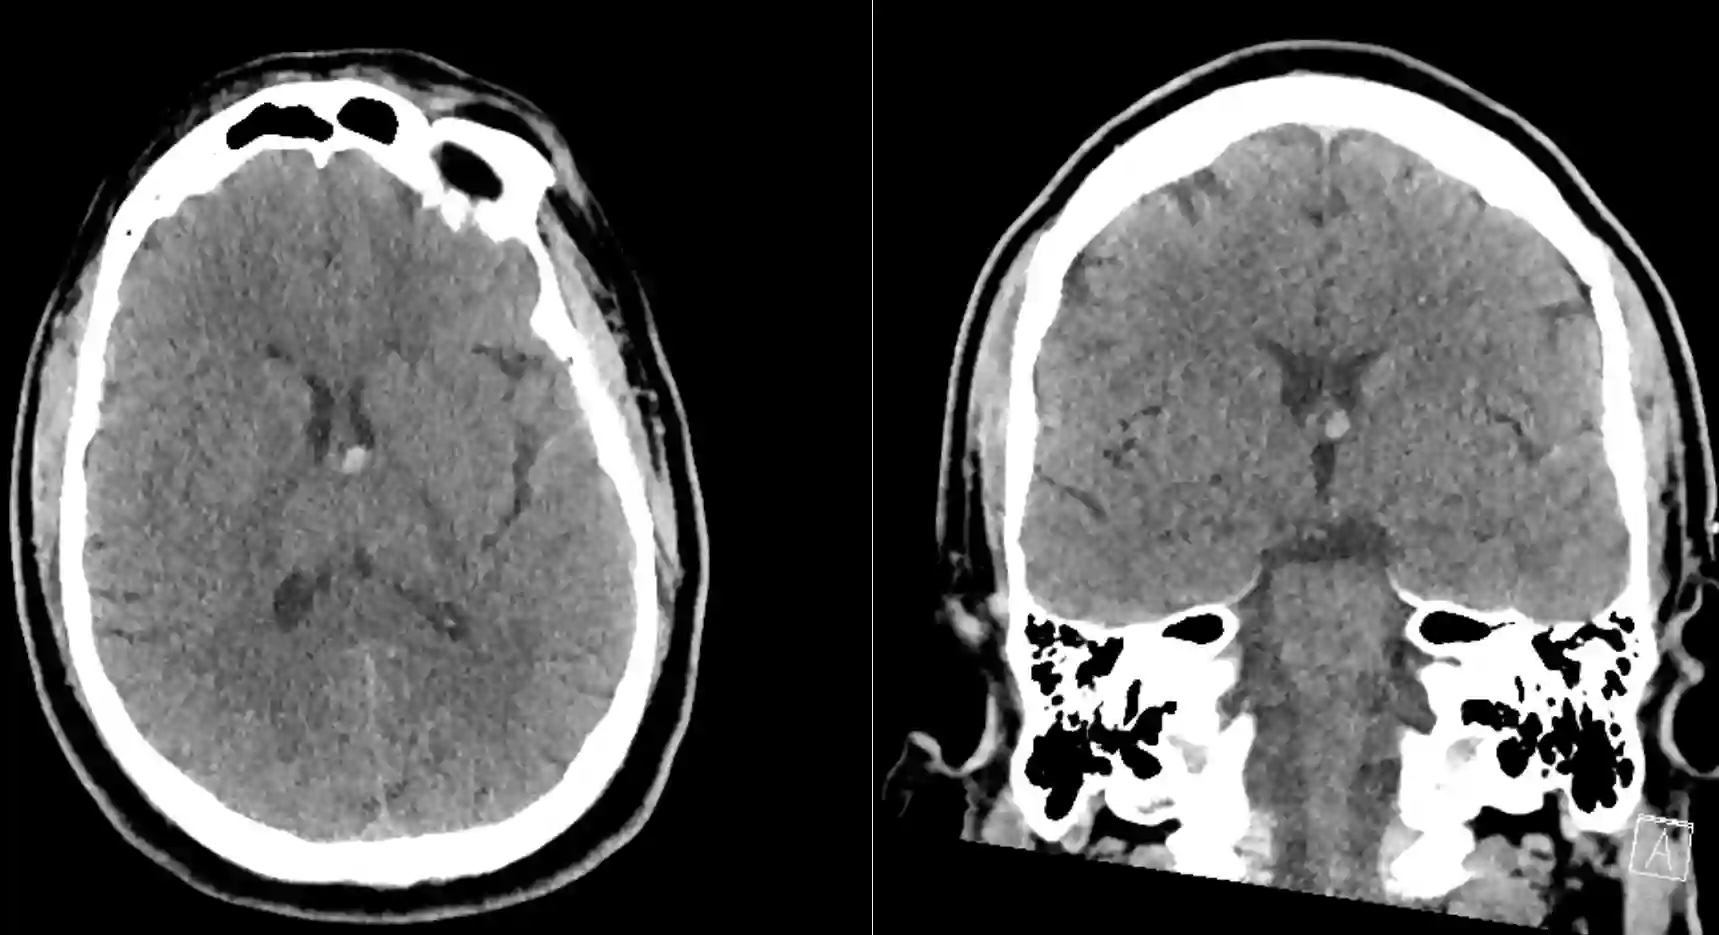

Kolloidzysten können in einer CT oder MRT Bildgebung dargestellt werden, wo sich die Zyste üblicherweise im anterioren Anteil des dritten Ventrikels befindet. In der MRT als auch CT Bildgebung zeigen sich Kolloidzysten variabel jedoch üblicherweise wie folgt[^2]:

CT Bildgebung

Kalzifizierungen werden bei Kolloidzysten nur selten beobachtet[^2].

CT nativ | CT mit Kontrastmittel |

Hyperdens | Ca. 50 % zeigen ein leichtes Enhancement |